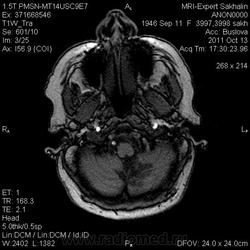

Ишемический инфаркт

ОНМК по ишемическому типу в бассейне правой СМА. Судя по очагам накопления в коре, подострое.

Последствия ОНМК с геморрагическим пропитыванием справа. Кистозно-атрофические изменения в левой гемисфере мозжечка (последствия ОНМК ). Множественные очаги сливного характера вещества головного мозга ( поля лейкоариоза)

Да хотела еще добавить возможно у пациента еще были лакунарные инсульты. В области базальных ядер( слева ) определяются кисты, окруженные глиозом. И на предпоследнем изображение в правой гемисфере мозжечка по- моему и также есть нмк.

Танюша, все указала-и лакунаные постишемические кисты, и кистозно-глиозные левой гемисферы мозжечка.Правая , вроде бы, не задействована в процессе.